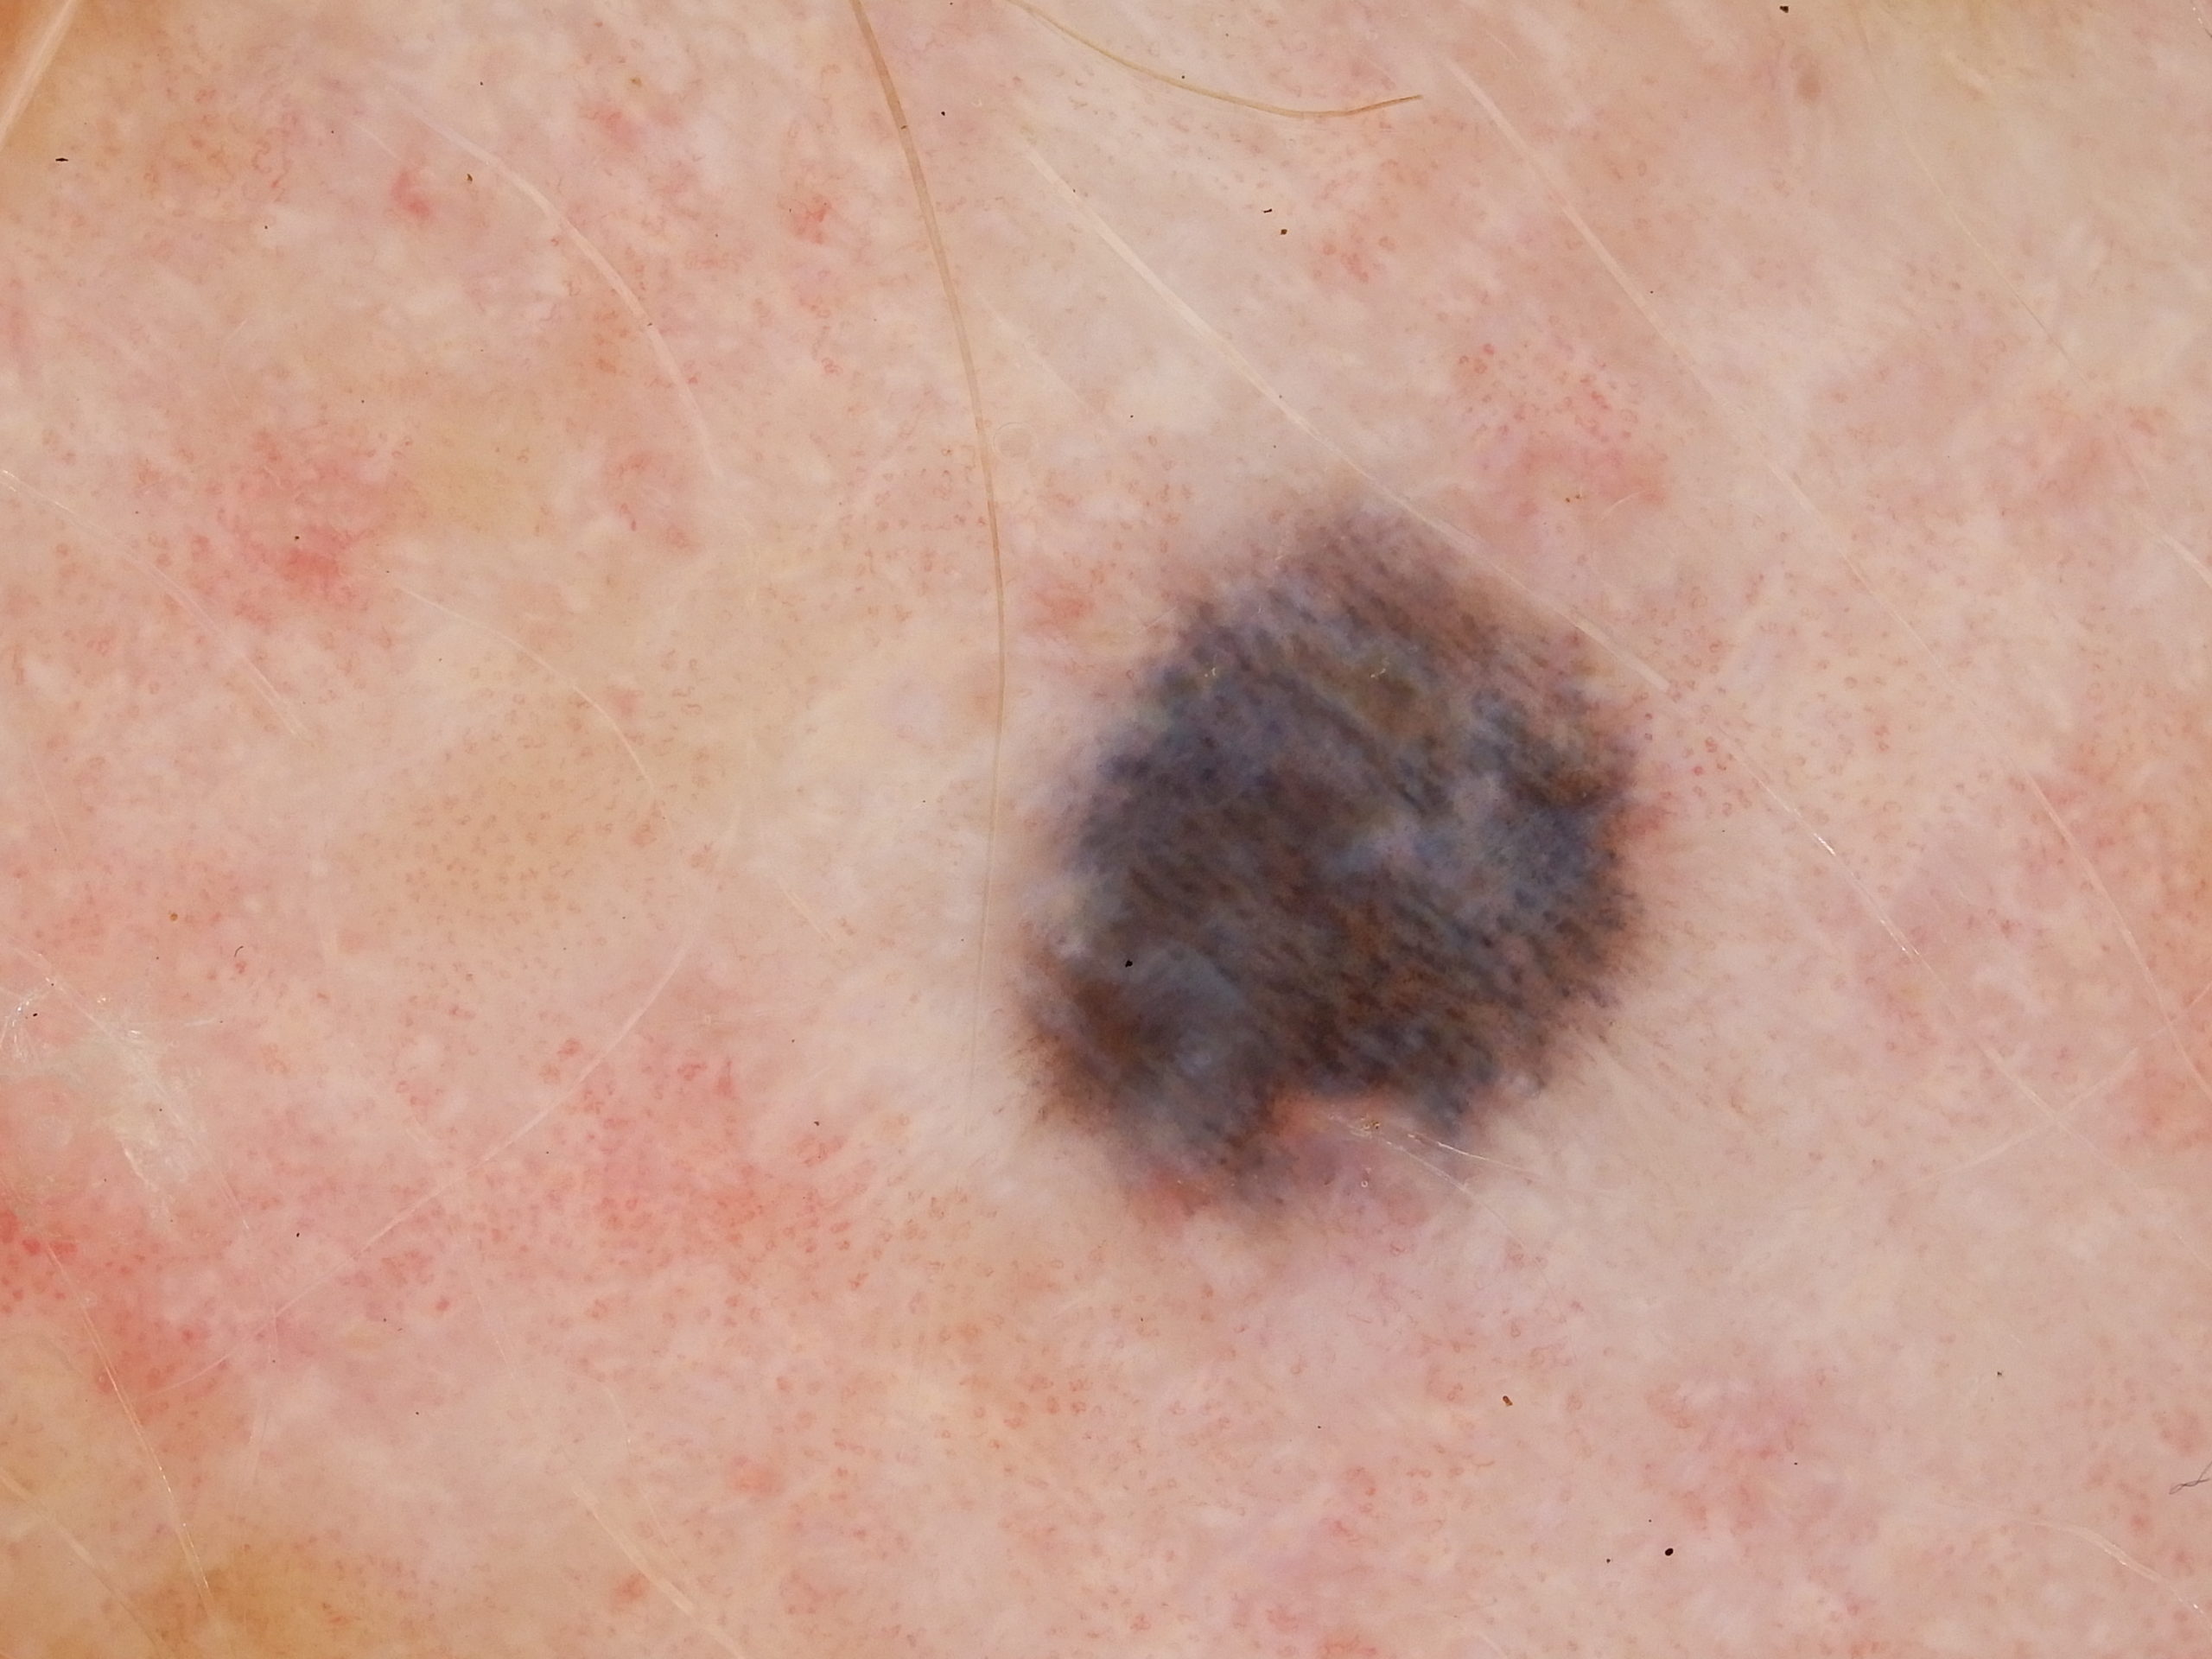

Site: Ankle

Diagnosis: Post Inflammatory Hyperpigmentation

Description: Note the perilesional hypopigmentation

These lesions arose after he went on Check Point inhibitor for metastatic melanoma. Note the perilesional hypopigmentation as well as the post inflammatory hyperpigmentation which was all that was left of his melanoma metastases. These had been stable for the last 9 months with no evidence in PET scans of melanoma elsewhere. This rteally shows the effectiveness of these immune stimulating drugs in metastatic melanoma.